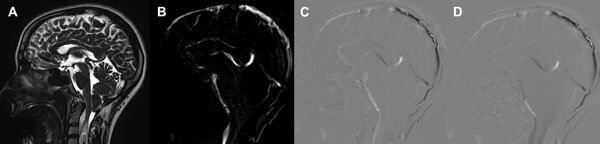

Estas secuencias permiten una evaluación cualitativa con valoración subjetiva del pasaje del LCR a través de las cisternas (Figura 1) y una valoración cuantitativa de la velocidad (Figura 2). La adquisición de las mismas se realiza de forma coordinada con el latido cardíaco (gatillado mediante el censado por el electrocardiograma o curva de pulso).13

Figura 1: Evaluación cualitativa en RM con técnica de contraste de fase. A: Imagen ponderada en T2 de alta resolución de cortes finos (3mm) que muestra el descenso amigdalino a través del foramen magno, el compromiso de las cisternas peritroncales y una siringomielia con imagen de turbulencia de flujo en su interior. B: Imagen en secuencia de fase que utiliza el contraste entre negro y blanco mostrando con señal hiperintensa el flujo de LCR cisternal C: Imagen de magnitud en fase anterógrada que muestra con señal hiperintensa el flujo en sístole. D: Imagen de magnitud en fase retrógrada que muestra con señal hipointensa el flujo en diástole. Con la valoración de estas secuencias en su totalidad y en reproducción en cine de las imágenes estáticas se logra la evaluación del pasaje de LCR a través de las cisternas peritroncales y los forámenes del cuarto ventrículo.